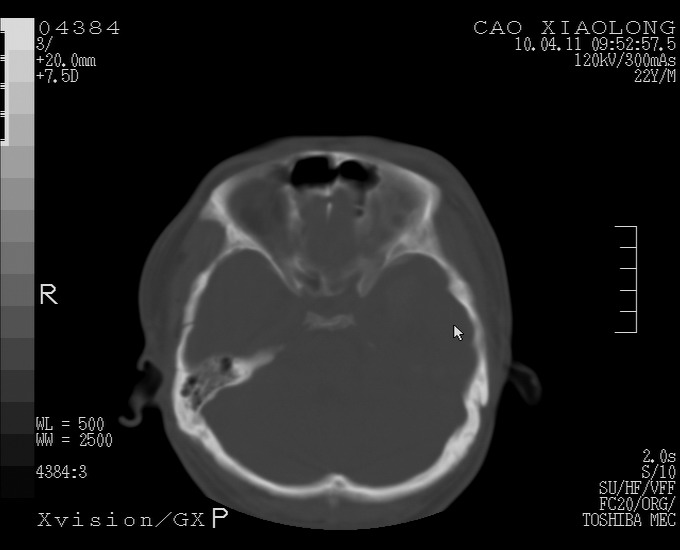

以下是引用随光逐影在2010-4-11 11:00:00的发言:[br]1)左侧额颞顶部硬膜下血肿。2)蛛网膜下腔出血。3)右侧颞顶部颅骨线形骨折。[br][br]20小时后复查:左侧额颞叶脑挫裂伤;左侧额颞顶部硬膜下血肿及蛛网膜下腔出血有吸收表现;右侧颞顶部颅骨线形骨折。[br]